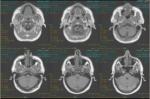

v    Imaging